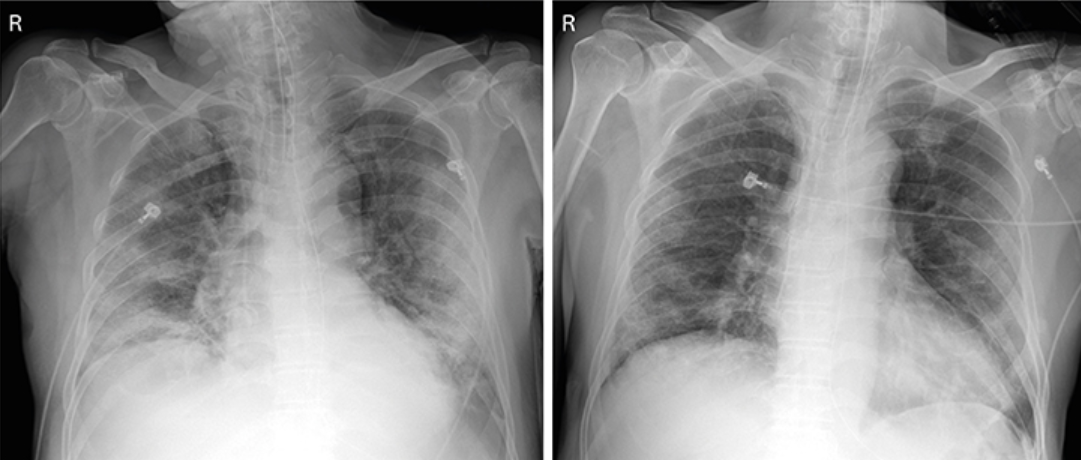

The first case, a 71-year-old man, has been treated with antimalarial and HIV drug, but his symptoms worsened.

The respiratory rate was over 30 times per minute (normally under 20 times per minute) and chest radiographs showed critical pneumonic symptoms in both of his lungs.

C-reactive protein (CRP) was up at 172.6 mg/ L (normally less than 8 mg/ L).

When the second case, a 67-year-old woman, was hospitalized, her respiratory rate was at 24 times per minute and oxygen saturation was at 93 percent (normally over 95 percent), while her CRP elevated up to 314 mg/ L with signs of lymphopenia.

Regardless of using corticosteroid on top of administering antimalarial and HIV drugs, the female patient sustained lymphopenia and the viral titer was increased.